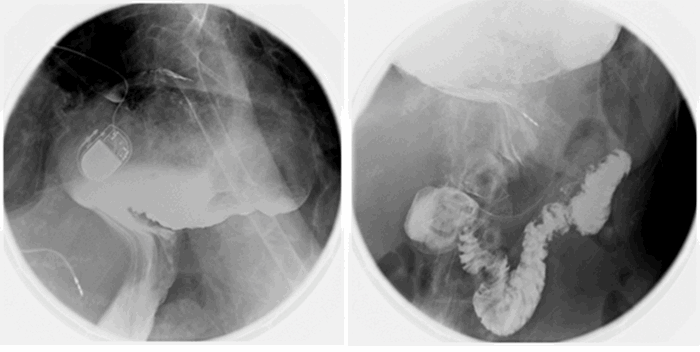

Computed tomography (CT) from outside facility performed earlier in the week revealed gastric outlet obstruction (GOO) caused by a massive type III PEH (Figure 1–4). She was subsequently discharged from this facility as she did not want surgical intervention and opted for hospice care. She presented to the ED later that week for persistent pain. At this time, it was decided to obtain a barium swallow instead of the repeat CT, demonstrating an intrathoracic stomach with concern for underlying gastric volvulus (Figure 5). Due to worsening obstructive symptoms, pain, and evidence of gastric outlet obstruction with possible gastric volvulus, it was recommended she undergo surgical intervention that day.

Figure 5. Preoperative barium swallow demonstrating dilated intrathoracic stomach with GOO and concern gastric volvulus due to lack of gastric emptying.

At her two-week follow-up, she was progressing very well without complication. A barium swallow was obtained (Figure 6), revealing a large, dilated, fluid-filled hiatal hernia with herniation of gastric fundus and proximal gastric body without evidence of obstruction and with prompt gastric emptying. No additional plans for repair of her hiatal hernia were made at this time. It was recommended that the patient follow up with cardiology to discuss TAVR prior to any elective repair.

Figure 6. Postoperative (three weeks) barium swallow demonstrating hiatal hernia with herniation of gastric fundus and proximal gastric body with prompt gastric emptying without evidence of obstruction.

It is important to note that endoscopic reduction of a PEH with gastropexy using PEG and T-fasteners does not repair the PEH (Figure 6). This technique does reduce the volvulus, relieve the GOO, and may reduce a portion of the herniated stomach, as seen in our case. The use of double PEG tube insertion for fixation of the stomach to the anterior abdominal wall has also been described in the literature as an effective treatment for reduction of symptomatic PEHs in this high-risk population.1 These techniques are ideal for elderly patients deemed high risk for surgery who need acute management of their PEH. These techniques are low-risk due to endoscopic approach and can be performed by surgeons in the emergent setting who do not necessarily have experience with formal laparoscopic or open PEH repairs. Additionally, these repairs do not require manipulation of the esophageal hiatus that renders elective definitive repair easier if needed once the patient is medically optimized and cleared for elective surgery.